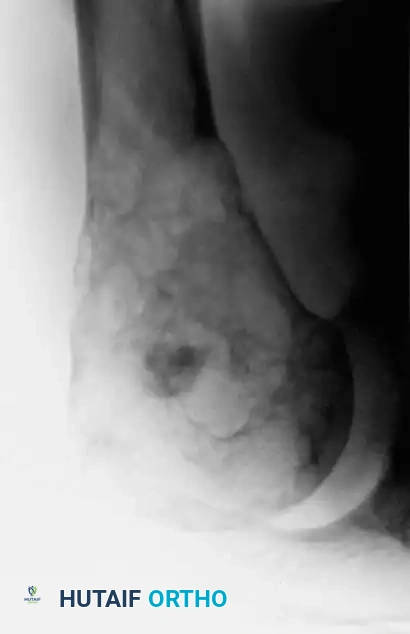

Image

Fig. 22-7 A: Anteroposterior view of the proximal humerus in a 47-year-old man with conventional chondrosarcoma. Note the central calcification and extensive cortical erosion.

Compared to benign enchondromas, chondrosarcomas exhibit a much more aggressive radiographic phenotype. Key malignant features include:

1. Deep Endosteal Scalloping: Erosion of more than two-thirds of the cortical thickness.

2. Cortical Destruction: Frank breakthrough of the cortex.

3. Periosteal Reaction: Often multi-layered or demonstrating a Codman's triangle in high-grade lesions.

4. Soft-Tissue Mass: Indicates extraosseous extension.